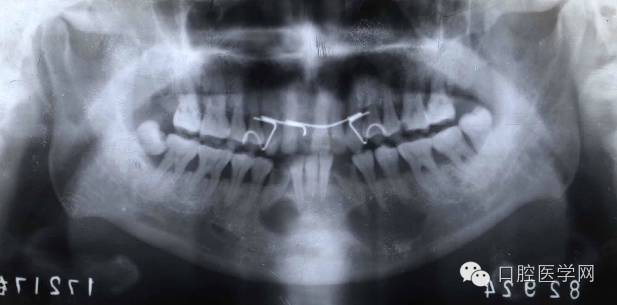

临床表现:好发于20岁以上女性,好发于下颌切牙的根尖部位。

早期:边界清楚、累及多个牙

第二期:骨质破坏区可见点状或团状钙化影

第三期:根尖区界限清楚、高致密度钙化影,牙周膜间隙及骨硬板清楚。